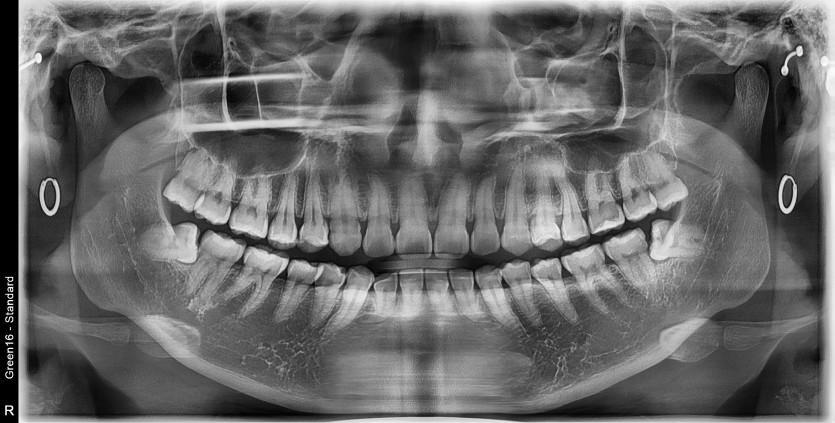

#18,28,38,48 사랑니 발치

구강 외과 전문의가 당일 발치했습니다.